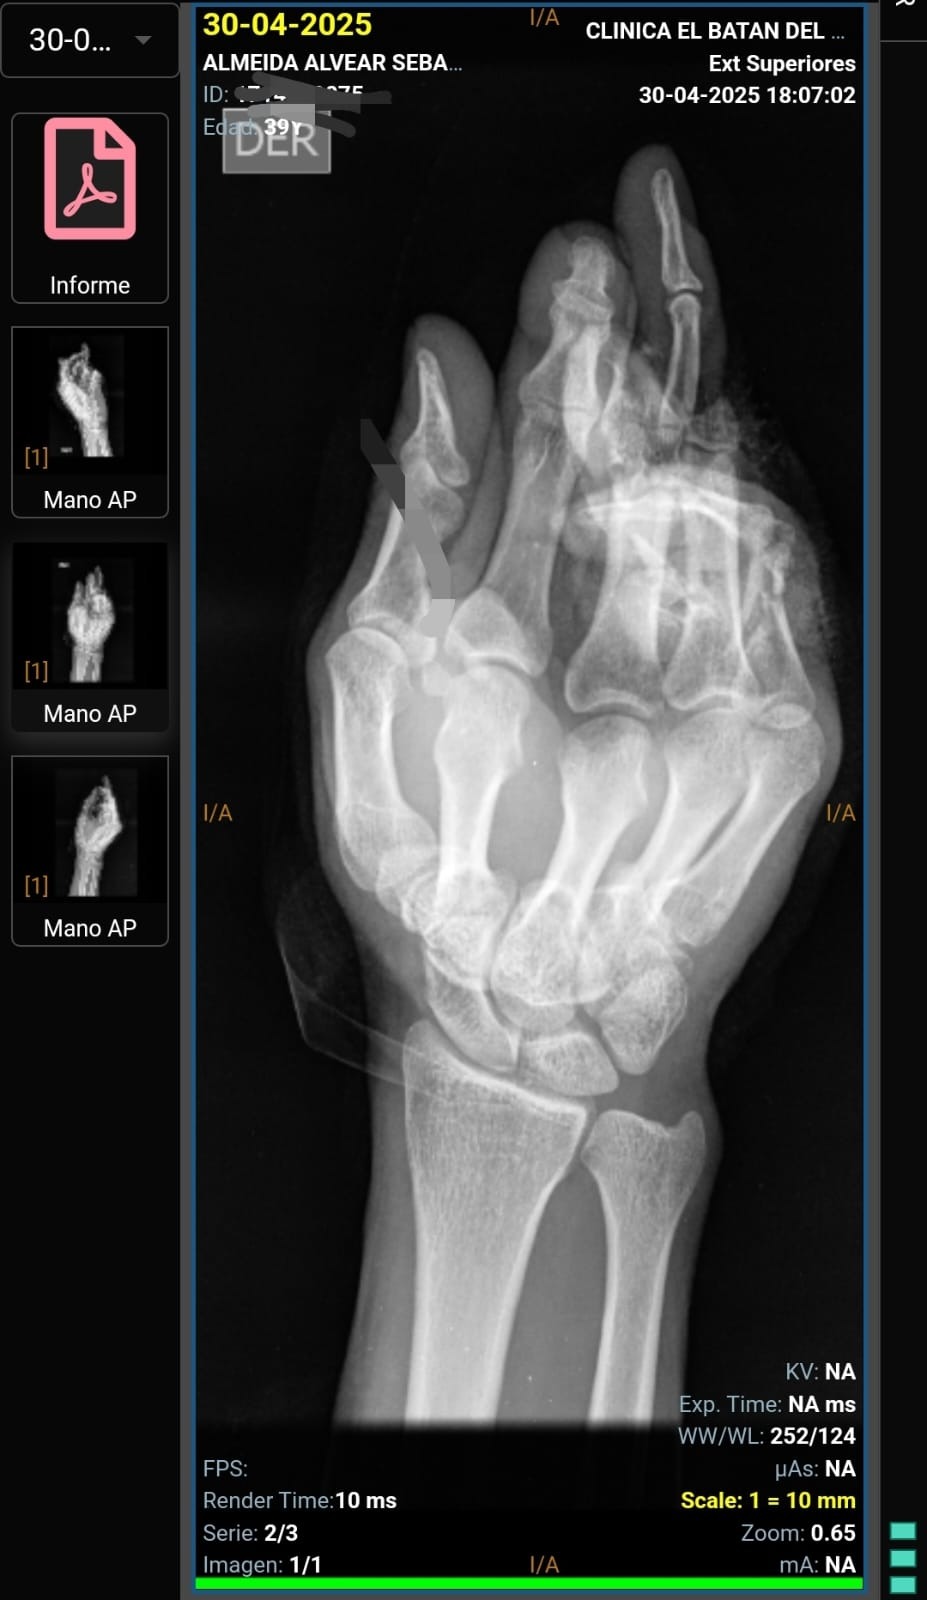

A few weeks ago, I suffered a serious accident with a circular saw. A mechanical failure led to the injury of three fingers on my dominant hand. I lost one finger, underwent an 8-hour surgery, and thanks to a skilled medical team, received a finger transplant and partial reconstruction. This experience has tested me deeply, but it has also shown me my own resilience.

Hace unas semanas, sufrí un accidente grave con una sierra circular que dañó tres de mis dedos. Perdí el dedo anular, me reconstruyeron el meñique, y gracias a una compleja operación lograron trasplantar un dedo a otro. A pesar de los altibajos emocionales y físicos, estoy decidido a salir adelante. Sin embargo, la recuperación me impedirá trabajar durante al menos 3 meses.